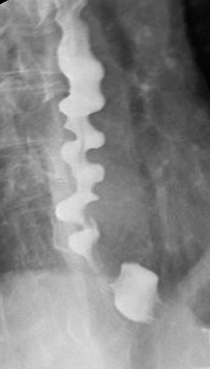

Diffuse esophageal spasm

Manometry: Intermittent peristalsis,multiple simultaneous contractions Esophagram: "Corkscrew" pattern

The diagnosis of DES is challenging due to the episodic nature of clinical features. Esophageal manometry reveals intermittent peristalsis and multiple simultaneous contractions of the middle and lower esophagus. The lower esophageal sphincter usually shows normal relaxation. Esophagram may show nonperistaltic contractions producing a "corkscrew esophagus" pattern, although this is neither sensitive nor specific. Endoscopy is usually normal. First-line treatment includes calcium channel blockers (eg, diltiazem), which relieve pain and reduce dysphagia.